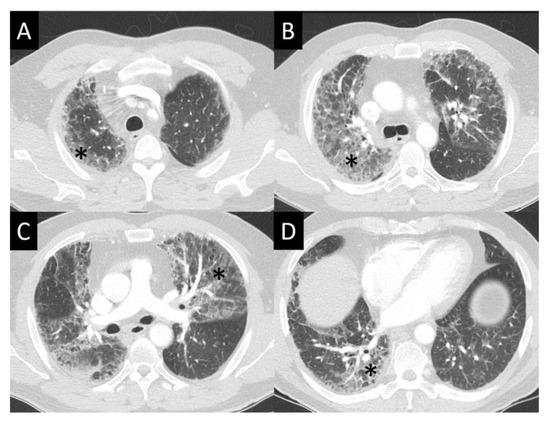

6.1.4. Chest Imaging